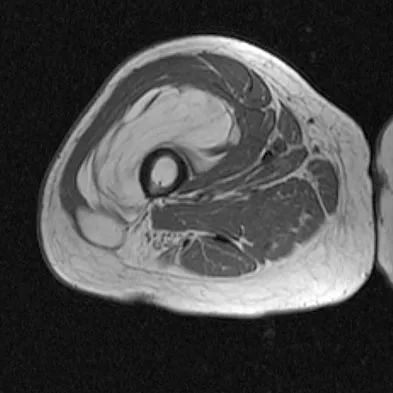

A 44-year-old recreational weight lifter reports chronic deep pain in his left shoulder that is aggravated by any pressing exercises. He also notes a painful catch in the shoulder occurring with rotational movements. Physical therapy and nonsteroidal anti-inflammatory drugs for 3 months have failed to provide relief. Examination reveals pain with O'Brien's test but no signs of instability. MRI scans are shown in Figures 4a and 4b. Treatment should now consist of

Explanation

The MRI scans show a large paralabral ganglion cyst in the spinoglenoid notch that communicates with an extensive tear of the glenoid labrum. Snyder and associates have classified superior labral tears into several subtypes that reflect the location and extent of the injury. Arthroscopic repair of the labral tear and aspiration of the ganglion cyst is the treatment of choice. Open excision of the cyst does not address the underlying problem of the labral tear. Snyder SJ, Karzel RP, Delpizzo W: SLAP lesions of the shoulder. Arthroscopy 1990;6:274-279. Piatt BE, Hawkins RJ, Fritz RC, et al: Clinical evaluation and treatment of spinoglenoid notch cysts. J Shoulder Elbow Surg 2002;11:600-604. McFarland EG, Kim TK, Savino RM: Clinical assessment of three common tests for superior labral anterior-posterior lesions. Am J Sports Med 2002;30:810-815.